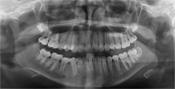

Digitale RöntgenEine der wichtigsten Untersuchungsmethoden des Zahnarztes ist schon seit Jahrzehnten das Röntgen - es zeigt die innere Beschaffenheit von Zähnen und Kiefer. Ein großer Teil der beginnenden Karies ist für den Zahnarzt nur im Röntgenbild erkennbar, da in vielen Fällen die Oberfläche der Zähne glatt ist und der Zahnschmelz auf den ersten Blick intakt aussieht.

Unsere Praxis verfügt über digitale Röntgengeräte, die gegenüber der konventionellen Methode enorme Vorteile bieten:

• Reduzierung der Strahlenbelastung um bis zu 90%, wodurch auch mehrere Aufnahmen keinerlei gesundheitliche Schäden verursachen

• die Röntgenaufnahme ist sofort auf dem Bildschirm zu sehen

• keine Umweltbelastung durch Chemieabfälle

• unkomplizierte Weiterverarbeitung am Computer

• Schneller Versand an Kollegen per Email